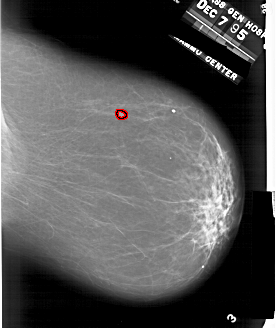

A_1863_1.LEFT_CC

LEFT_CC LINES 6646 PIXELS_PER_LINE 5086 BITS_PER_PIXEL 12 RESOLUTION 43.5 NON_OVERLAY

FILE: A_1863_1.RIGHT_CC.OVERLAY

TOTAL_ABNORMALITIES 1

ABNORMALITY 1

LESION_TYPE MASS SHAPE IRREGULAR MARGINS MICROLOBULATED

ASSESSMENT 4

SUBTLETY 4

PATHOLOGY BENIGN

TOTAL_OUTLINES 1

BOUNDARY